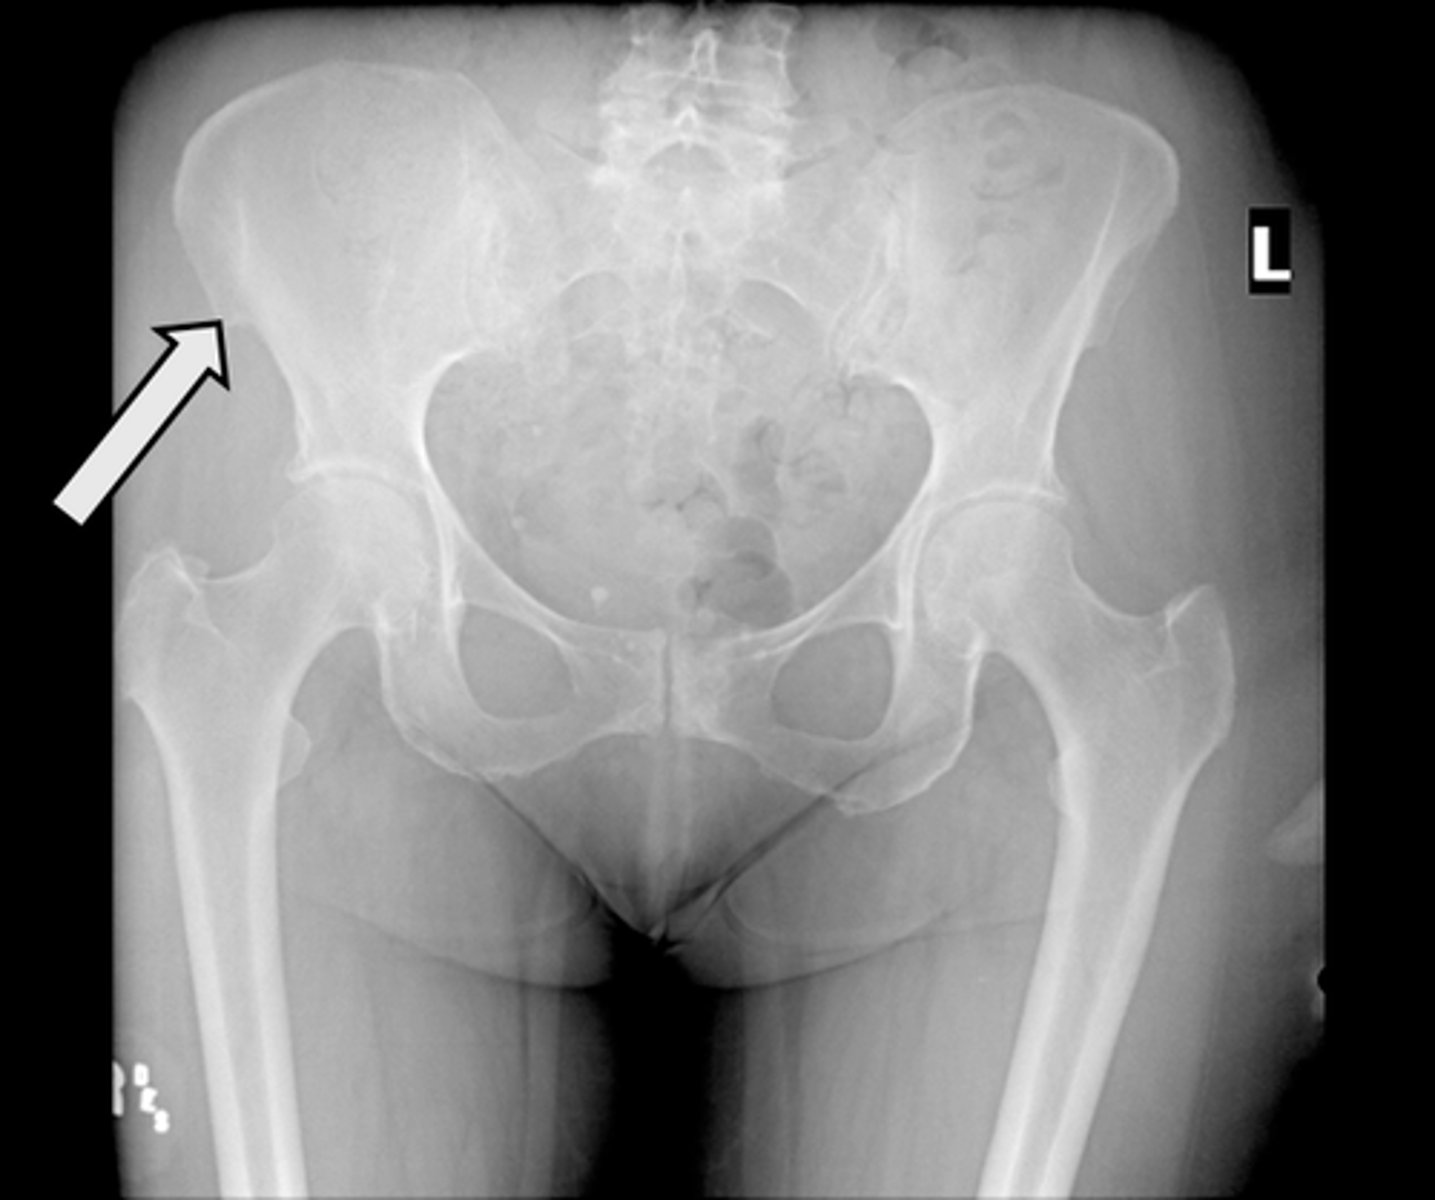

AP pelvis

What is the image?

L acetabulum

What is indicated in the image?

L anterior superior iliac spine (ASIS)

L ilium

L ischial tuberosity

L obturator foramen

L sacroiliac joint

L superior ramus of pubis

R acetabulum

R anterior superior iliac spine (ASIS)

R ilium

R ischial tuberosity

R obturator foramen

R sacroiliac joint

R superior ramus of pubis

Sacrum